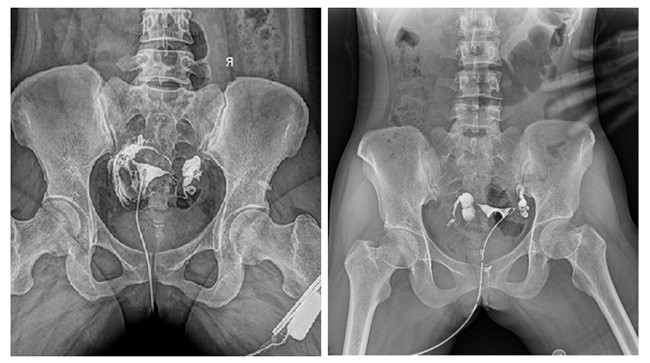

輸卵管造影檢查可根據(jù)造影劑在輸卵管及盆腔內(nèi)的顯影情況了解輸卵管是否通暢、阻塞部位及宮腔形態(tài),是超聲、CT、核磁、宮腔鏡、腹腔鏡、輸卵管鏡等所無法替代的。作為目前普放領(lǐng)域先進(jìn)的影像設(shè)備,平板動(dòng)態(tài)DR進(jìn)行子宮輸卵管造影檢查,大大超越了過去的檢查技術(shù),更加精準(zhǔn)、便捷、高效。

相較于傳統(tǒng)胃腸機(jī),動(dòng)態(tài)DR矩形采集面積大,一次曝光即可顯示整個(gè)盆腔,大幅減少觀察時(shí)間,可控的瞬時(shí)照射避免受檢者吸收過多的X線,對(duì)育齡期女性的檢查尤為重要。毫秒級(jí)時(shí)間內(nèi)高清點(diǎn)片,可以在造影劑流動(dòng)的過程中完成拍片,抓拍到關(guān)鍵圖像,更加清楚地了解到管腔的具體通暢情況及堵塞部位,對(duì)檢查及診斷有非常重要的價(jià)值。